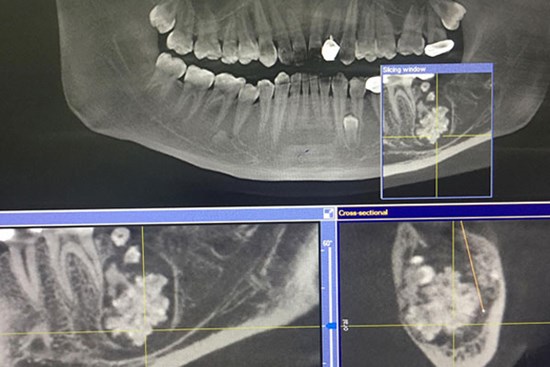

Bác sĩ gắp răng lúc nhúc trong miệng nam thanh niên Hà Nội

Nam thanh niên đi khám vì đau răng nhưng khi chụp X-quang, bác sĩ phát hiện bên dưới lợi lúc nhúc răng to nhỏ.